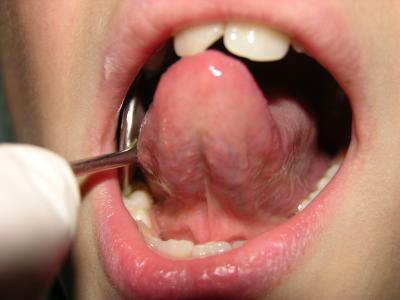

En la línea media se observa el frenillo lingual. En su base a lado y lado se observan 2 orificios, carúnculas sublinguales-

En la línea media se observa el frenillo lingual. En su base a lado y lado se observan 2 orificios, carúnculas sublinguales- carúnculas salivales, representadas por los conductos de las glándulas submaxilar y sublingual (provoca elevación de la zona).

El frenillo de lengua es una cuerda de membrana    mucosa que va de la mitad de la cara inferior de la lengua (cara sublingua

El frenillo de lengua es una cuerda de membrana mucosa que va de la mitad de la cara inferior de la lengua (cara sublingual) hasta el piso de la boca. (Marchesan 2010)